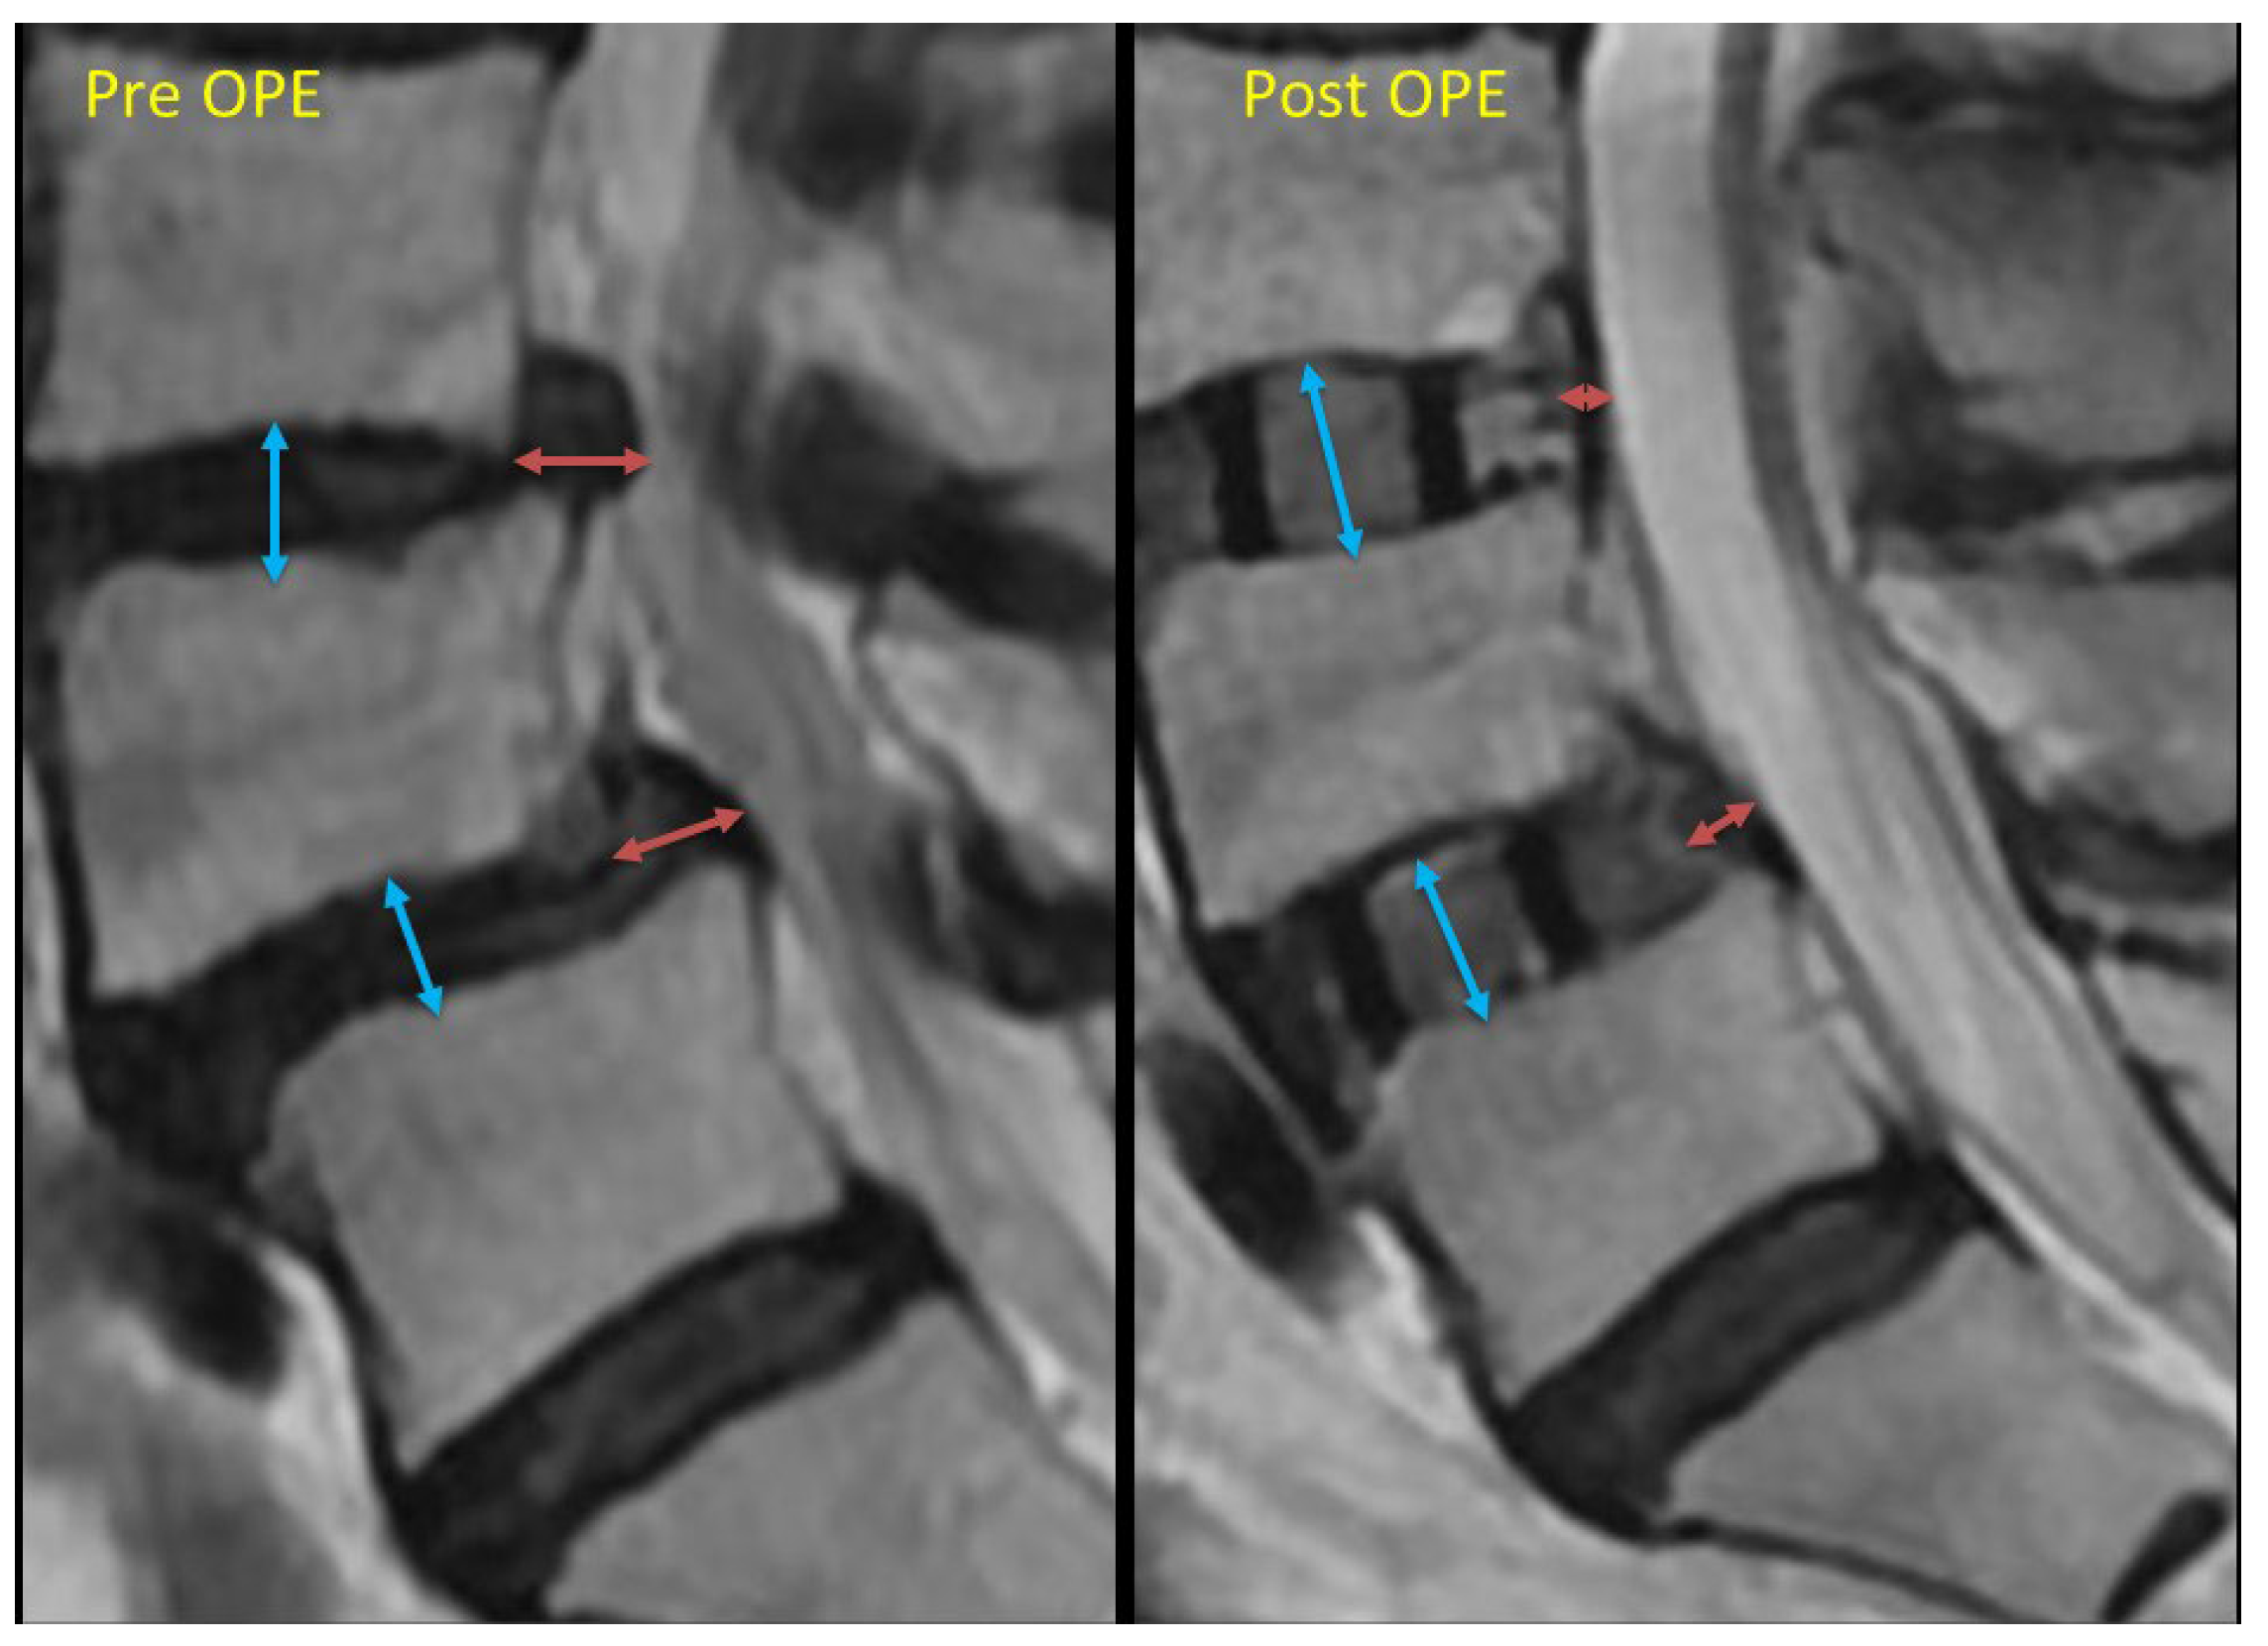

The measurement objects were the backward bulging length and the intervertebral height extension length. The definition for the backward bulging is the maximum posterior bulging length from the posterior surface of the vertebral body located forward at the level of the intervertebral disc (Figure 1).

If this backward bulging shortening was larger than 3 mm, we defined it as large shortening. We also measured the intervertebral height extension and divided it into these 3 groups: less than 3 mm, more than 3 mm, and 4 mm (Figure 2).

Figure 2. This is the schema of the “backward bulging” length measurement. The red arrow indicates the backward bulging length. We measured the difference between pre- and post-operation measurements. If this backward bulging shortening exceeded 3 mm, we defined it as significant shortening. The blue arrow indicates the “intervertebral height”. Post-operation, this height equals the size of the cage. We also measured the difference as the “intervertebral height extension”. These measurements were then divided into three groups: less than 3 mm, more than 3 mm, and 4 mm.